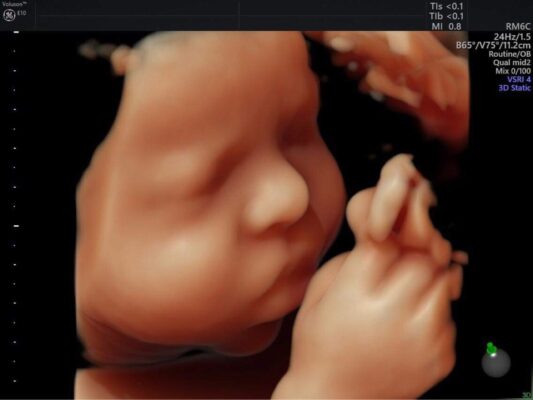

B. Siêu âm 3D/4D

Siêu âm 3D/4D là một loại siêu âm nâng cao hơn, cho phép tạo ra hình ảnh 3 chiều của thai nhi. Với siêu âm 4D, bác sĩ có thể xem được hình ảnh chuyển động của thai nhi, giúp cho việc giám sát sự phát triển của thai nhi trở nên chính xác hơn.

Hình ảnh kết quả siêu âm 4D